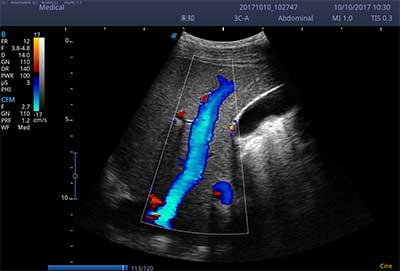

E3便携式彩色多普勒超声诊断系统拥有专业超声技术平台、高度集成化的硬件模块和结构设计、简便的操作流程、支持三探头接口全激活,兼顾了优质图像、轻便机身以及台便两用的临床使用需求。无论在常规超声科门诊检查,还是在急诊、麻醉、ICU、户外等各种应用场景。都能给您带来流程的操作体验。

• SR Flow 高分辨率血流